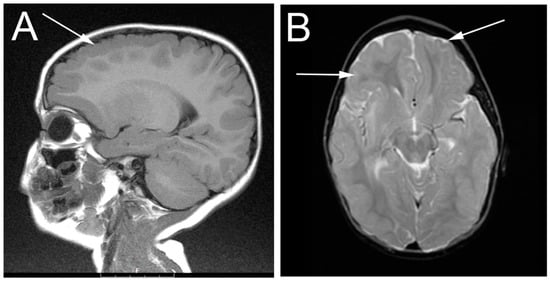

Early behavioral intervention started at eight months. The girl became able to sit independently by two years of age, and walk at three years of age. She began to speak single words at age two, and simple sentences around age six. The patient presented for neurological evaluation at two years of age with concerns for seizures. As her routine EEG was normal, no antiseizure medication was prescribed. Muscle biopsy demonstrated neuropathic changes with large fiber groups consistent with denervation/re-innervation. Nerve conduction/EMG studies were not performed. Electroencephalogram (EEG) analysis at that time revealed diffuse bilateral epileptiform discharges with a bifrontal predominance. Magnetic resonance imaging (MRI) of the brain demonstrated symmetric bilateral polymicrogyria of the frontal lobe involving the superior and middle frontal gyri. There was hypo-myelination of subcortical white matter associated with the dysplastic areas. No other areas of polymicrogyria were seen and otherwise the brain, ventricles, and extra-axial spaces were normal in appearance (Figure 1).

Figure 1.

Magnetic resonance imaging (MRI) imaging of the patient at two years of age showing frontal lobe bilateral polymicrogyria (highlighted by arrows). (A) sagittal plane; (B) transverse plane.